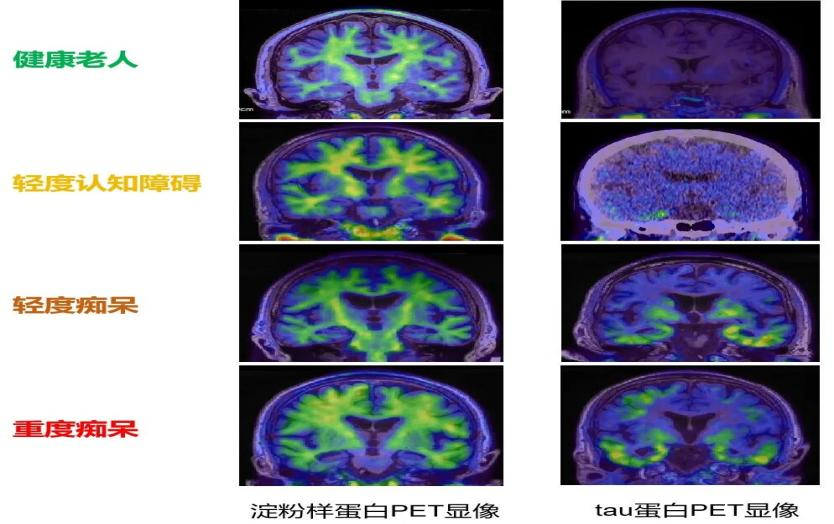

常规核磁共振(MRI)可清晰显示脑萎缩和海马体缩小,为阿尔茨海默病诊断提供基础依据。而更精准的PET检查(如Amyloid PET/Tau PET)能够无创探查脑内β-淀粉样蛋白斑块和Tau蛋白缠结的部位和程度,可将阿尔茨海默病的早期诊断时间,大幅提前15~20年,也可以评估疾病的严重程度。